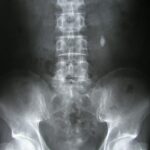

If one is to actually look at the literature on this topic, they will find out “abnormalities” of the spine (bulges or otherwise) are found in people without issues a crazy high percentage of times. Boden and colleagues found “degenerative changes” (i.e. normal aging) in 59% of individuals between the ages of 40 and 60. Another group, Brinjikji et al noted 50% of healthy individuals in their 40’s had a disc bulge and another 33% had at least 1 “herniated” disc. Clearly if such a high percent of people without back pain have these “abnormalities” then how can we TRULY equate these changes on imaging to ANY person’s problems? The answer is WE CAN’T!!!

It will end when people are ready to actually confront their back pain, take ownership, and not look for someone else to “FIX” their issue. To not demand imaging to find something, because chances are IT won’t change the treatment plan or outcome. It will end when doctors stop over-imaging patients with just back pain and actually follow the medical guidelines (they were created for a reason). This is not meant to dismiss those suffering with back pain, but there are very specific reasons for imaging the spine and short of those findings, imaging is not advised. In fact, imaging when not advised can cause more harm than good per Flynn et al.